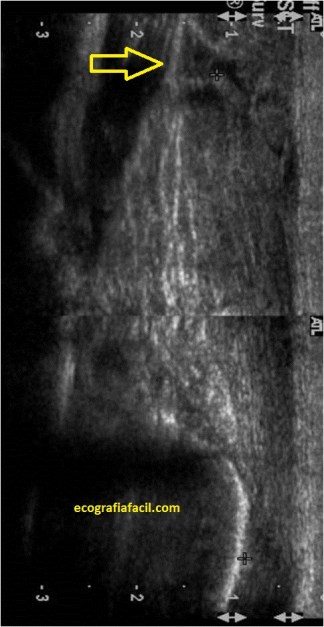

La/el paciente en decúbito prono con el pie «colgando» fuera de la camilla de exploración y con un ángulo de 90º entre el eje largo de tibia con el eje largo del pie. Mira:

El ángulo correcto lo marca la línea roja que ves en la imagen superior.

La posición de la sonda será sobre el eje largo del tendón, que en ocasiones será muy fino y habrá que mantener la estabilidad de la sonda apoyando levemente el 5º dedo de la persona que ejecute la prueba sobre la piel de la/el paciente para mantener correctamente posicionado el transductor y además debemos asegurarnos de ver todo el tendón desde la parte proximal del tercio medio de la pierna hasta la inserción en el calcáneo tanto en longitudinal como en transversal…

Coloca la sonda donde están las letras de ecografiafacil.com